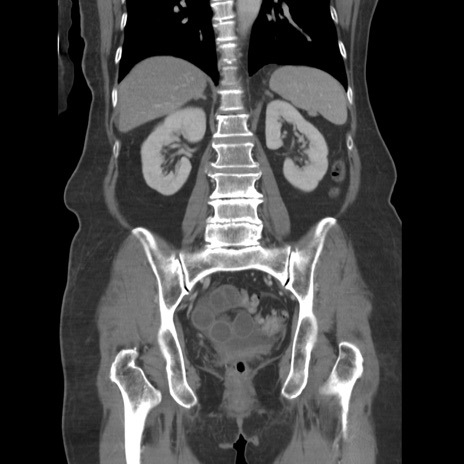

横断像

【症例】80歳代女性

【主訴】下腹部痛

【現病歴】約8時間前より下腹部痛の出現あり、救急外来受診。

【既往歴】両側付属器切除

【身体所見】意識清明、下腹部正中に手術痕あり、その部位に一致して圧痛と反跳痛あり。腸蠕動音は亢進。

【データ】WBC 9300、CRP 0.15